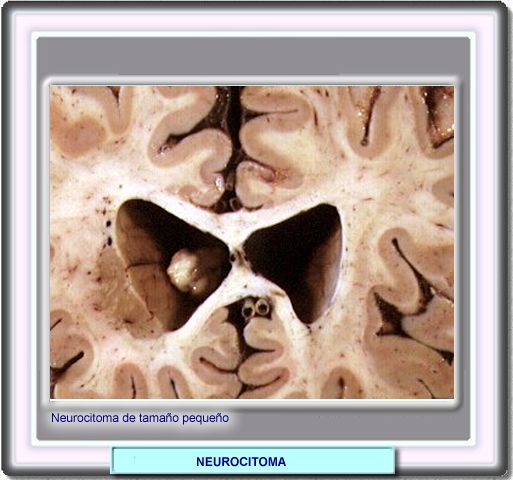

NEUROCITOMA [ICD-10:  (M9506/0)]

En la mayor parte de los casos, se trata de un tumor de desarrollo corto (los síntomas clinicos aparecen en menos de 8 meses), pero en algunos casos, los síntomas pueden estar presentes hasta 3 años y en algunos casos, tumores de pequeño tamaño han descubiertos accidentalmente.

Macroscópicamente, el tumor está bien circunscrito desmacándose de los tejidos que le rodean. Aproximadamente un 40% de los mismos tienen una textura arenosa debida a numerosas microcalcificaciones